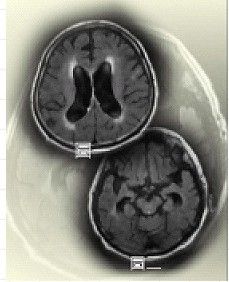

水腦症是指腦室積水。人腦的構造除了一般常聽說的血液循環外,還有所謂腦脊髓液的循環。腦脊髓液像血液循環一樣,在大腦構造內是流通的。這方面在大腦的詳細構造,有所謂的“腦室”或是“腦池”,就像是水庫或是池塘一樣的構造,在一般的電腦斷層上可以很清楚的看到。

腦水在這些池塘或水庫是流動的,腦水由腦中央的腦室,流過大腦的表面,以及腦池,然後在頭頂吸收。如果流通的路線被阻塞了,那么水庫或是腦池的水會漲大起來,腦壓會升高,腦會受到壓迫,人就會變得反應遲鈍。這就是所謂的水腦症。俗稱腦內積水。

正常顱壓腦積水(NPH)是交通性腦積水的一種特殊形式,表現為腦室擴大,伴有間歇性腦脊液壓力增高。其診斷只有通過持續腦室內壓力記錄(24小時以上)才能得出,腦室壁彈性改變,以及腦脊液粘性增強,都可能是正常顱壓腦積水的發病機理。